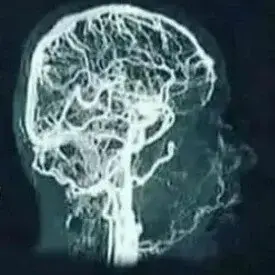

An MRA scan is a picture of the blood vessels, in this case the cerebral blood vessels.

MRA stands for Magnetic Resonance Angiography.

It is a combination of angiography (X-ray examination of blood vessels) and an MRI scan (powerful magnetic field and radio frequency waves).

Sometimes a contrast fluid is injected into the blood vessels so that they become clearly visible during the scan.